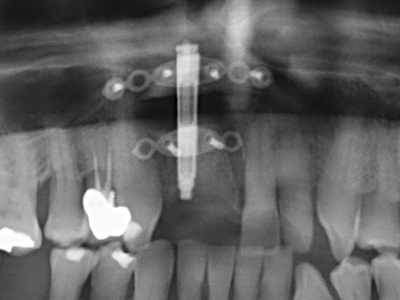

Abb. 11: Das postoperative OPTG veranschaulicht die vertikale Augmentation und Sinusbodenelevation.

Abb. 12: Nach sechs Monaten Heilungsperiode zeigt sich ein in allen Richtungen ausreichend dimensionierter, vitaler Kieferkamm.

Die Präparation des lateralen Fensters bei der externen Sinusbodenelevation stellt gerade für chirurgisch unerfahrene Implantologen eine große Herausforderung dar. Die knöcherne Bedeckung der Kieferhöhle ohne eine Verletzung der darunterliegenden Schneider’schen Membran abzutragen ist dabei nur ein Teil der Operation – nach Schaffung eines ausreichenden Zugangs muss die Kieferhöhlenschleimhaut vorsichtig mobilisiert werden, um Raum für das einzubringende Material bzw. die Implantate zu schaffen. In dieser Indikation ist die Piezochirurgie zweierlei hilfreich: zum einen kann durch Verwendung diamantierter Instrumente eine selektive Knochenabtragung erfolgen und die darunter liegende Schleimhaut bleibt bei vorsichtiger Vorgehensweise intakt. Zum anderen unterstützen die Ultraschallfrequenzen zusätzlich eine komplikationslose Ablösung der Schleimhaut – sie werden durch spezielle stumpfe Ansätze in den Spaltraum zwischen Schleimhaut und Kieferhöhlenboden übertragen (Cassetta, Ricci et al. 2012, Pereira, Gealh et al. 2014) (Rickert, Vissink et al. 2013). So erscheint es nicht verwunderlich, dass in aktuellen Übersichtsarbeiten über die externe Sinusbodenelevation neben der Verwendung von rauen Implantatoberflächen und dem Einsatz von Knochenersatzmaterialien auch der Einsatz von piezoelektronischen Geräten als positiv bewertet wird (Wallace, Tarnow et al. 2012).

Abb. 6: Nach Präparation eines Mukoperiostlappens wird der Zugang zur Kieferhöhle piezoelektrisch präpariert.

Abb. 7: Die initiale Präparation der Kieferhöhlenschleimhaut kann ebenfalls ultraschallunterstützt erfolgen.

Abb. 8: Nach erfolgtem Sinuslift wird der krestale Knochensplint auf dem defizitären Kieferkamm fixiert.

Abb. 9. Unterfütterung mit bovinem Knochenersatzmaterial (Cerabone 0,5-1mm, Botiss Biomaterials, Berlin) und Eigenknochen (palatinale Ansicht).

Abb. 10: Abdeckung des augmentierten Bereiches mit einer langzeitstabilen Perikardmembran (Jason Kollagenmembran, Botiss).